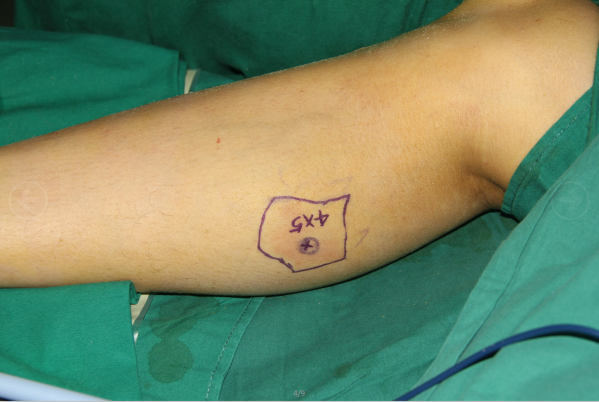

过完年后的第二个小皮瓣

腓肠内侧动脉皮支皮瓣,皮支与足背动脉端侧吻合